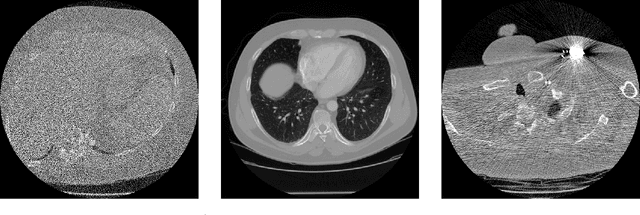

Abstract:Deep Learning approaches for solving Inverse Problems in imaging have become very effective and are demonstrated to be quite competitive in the field. Comparing these approaches is a challenging task since they highly rely on the data and the setup that is used for training. We provide a public dataset of computed tomography images and simulated low-dose measurements suitable for training this kind of methods. With the LoDoPaB-CT Dataset we aim to create a benchmark that allows for a fair comparison. It contains over 40,000 scan slices from around 800 patients selected from the LIDC/IDRI Database. In this paper we describe how we processed the original slices and how we simulated the measurements. We also include first baseline results.